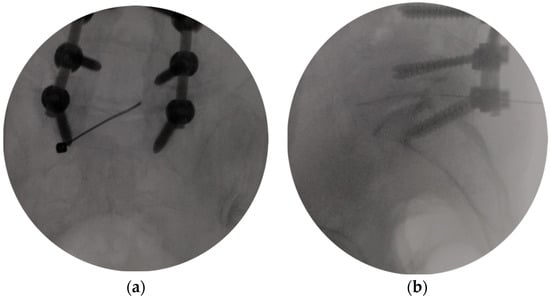

2.3. Surgical Procedures